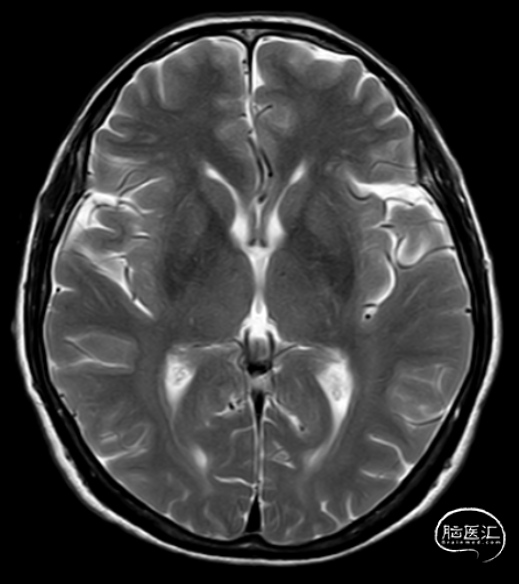

头颅MRI平扫

头颅MRI+MRA提示

5、脑动脉硬化;

6、脑白质病变。